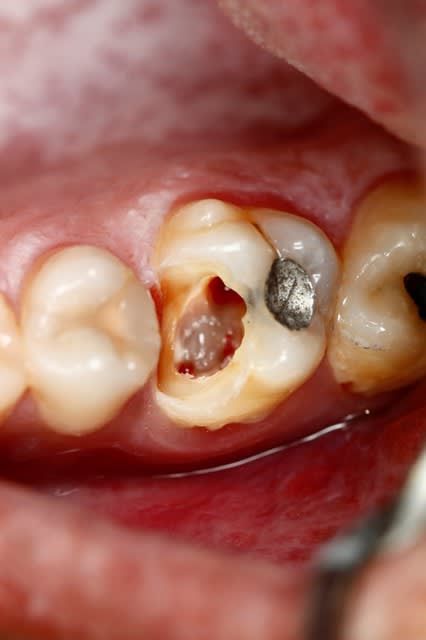

Pour ce cas que j'avais déjà exposé, c'est très intéressant...

Si dés le départ on décide de faire l'endo et couronne, on taille, on ouvre, et a la fin on se dit qu'on a bien fait de faire la couronne, vu qu'il reste pas grand chose. Au passage on perd beaucoup de résistance mécanique de la dent, et on descend toute les limites au niveau gingival ce qui dans le temps expose la limite à une contamination biologique, reprise de carie ...etc...

Ici, je fais l'endo en essayant de garder ce que je peux de la dent...

Ensuite a la fin de l'endo, c'est propre, j'ai un accès étanche, j'en profite pour coller et remonter la limite. C'est le meilleur moment pour le faire, non ? ... Et surement le meilleur moyen d'avoir une étanchéité sur la zone faible de cette dent, sa limite proximale infra gingival.